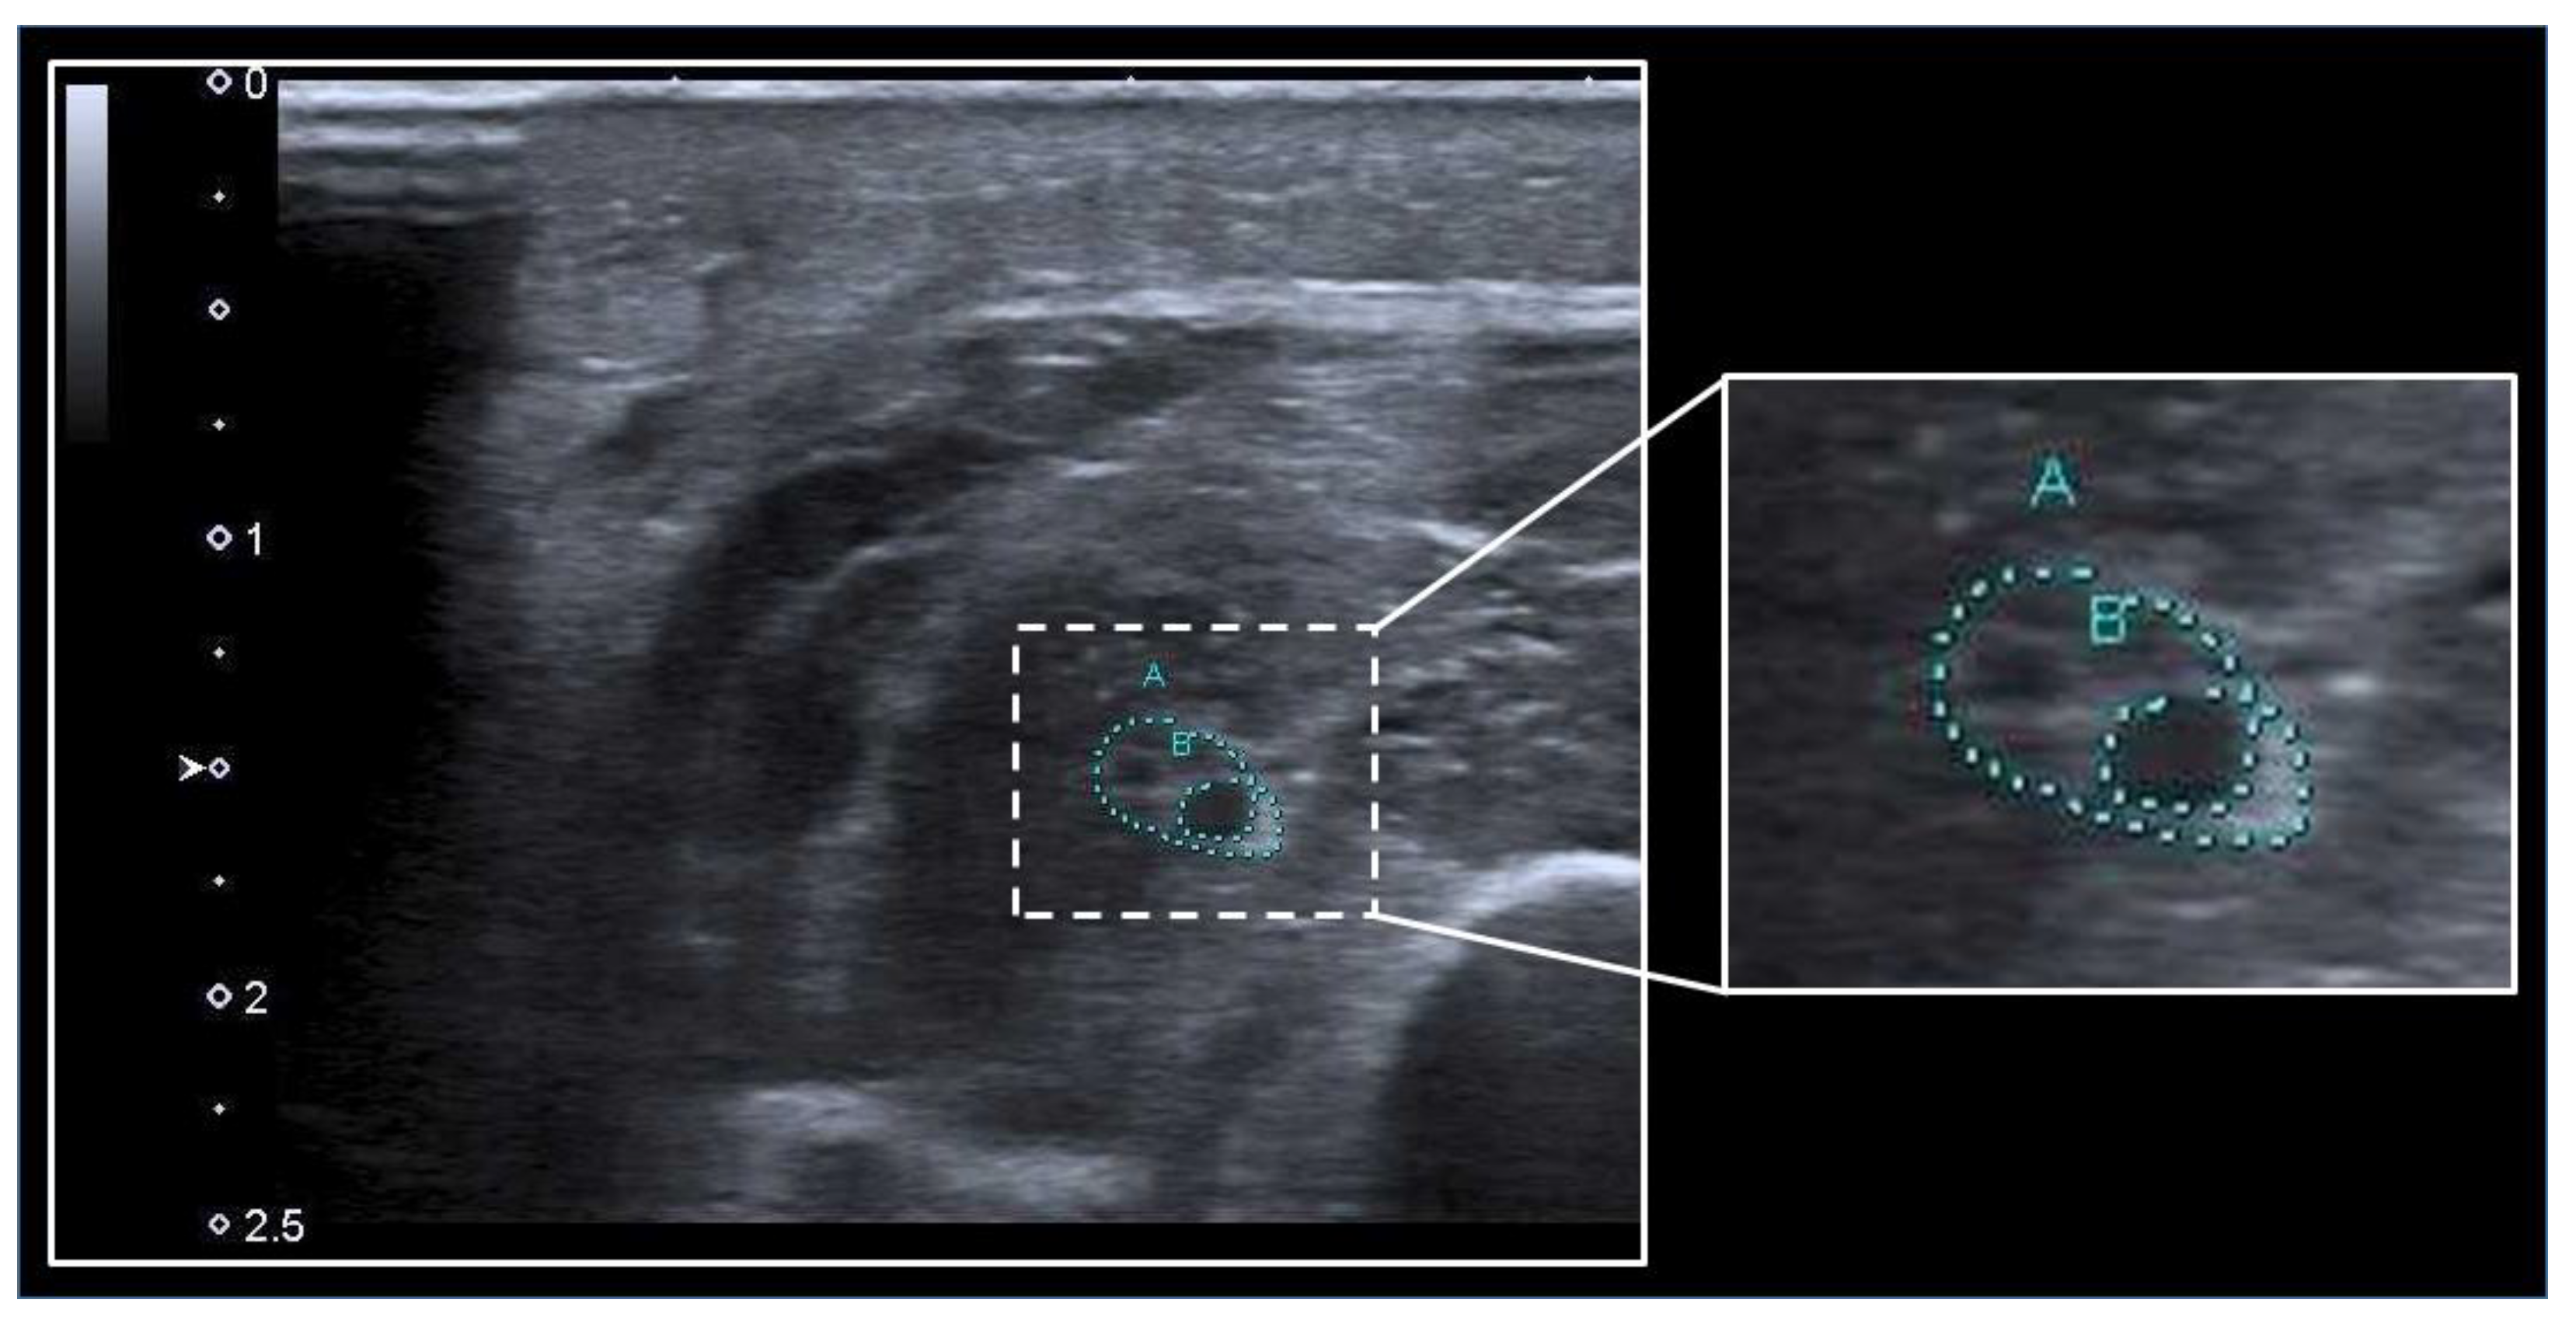

3.1. Skeletal Muscles

3.2. Peripheral Nerves